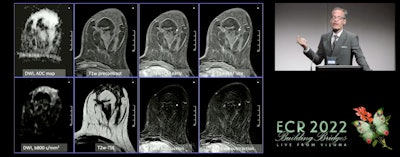

Baltzer said that he expects MRI protocols to be shorter in 2025, with a magnet time of less than 10 minutes. This, he said, can be accomplished with diffusion-weighted imaging (DWI) and T1-weighted dynamics. Acceleration techniques using artificial intelligence (AI) could also help in reconstructing images and abbreviated protocols, he added.

Other improvements Baltzer predicts will be implemented in 2025 include the usage of common lexicon, applying the Kaiser score when using machine learning for imaging, greater usage of DWI to help prevent unnecessary biopsies, more evidence in screening women with dense breasts and treatment response, and ending the usage of abbreviated first-pass imaging.